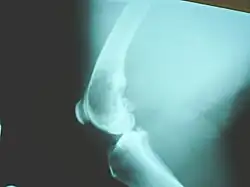

- Röntgenbild

Gerade das Auftreten im Jugendalter führt häufig zu Fehldiagnosen. Daher sollten Knochenschmerzen, gerade im Kniegelenk, spätestens nach vier Wochen mittels Röntgenuntersuchung kontrolliert werden.

Betroffen ist v. a. die mittlere Alterskategorie, wobei einige Studien auch eine Prädisposition für kastrierte Tiere beschreiben. Das Osteosarkom zeigt sich dabei klinisch meist als schmerzhafte Schwellung an den langen Röhrenknochen nach dem Grundsatz Ellbogengelenksfern – Kniegelenksnah. Auf einer Röntgenaufnahme ist dabei üblicherweise eine Knochenauflösung (Osteolyse) im typischen sunburst pattern zu sehen.